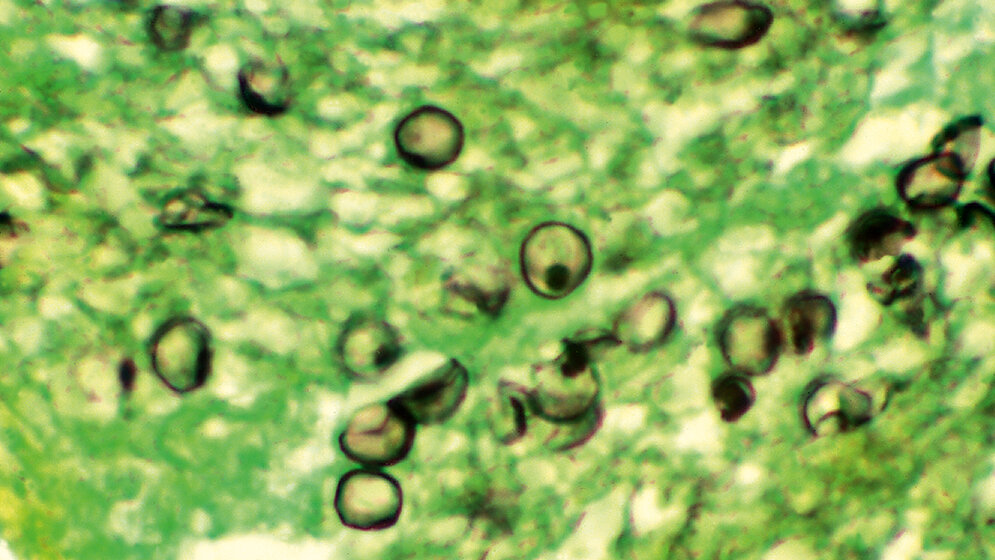

Heute besteht kein Zweifel mehr, dass Pneumocystis zu den Pilzen zählt, obwohl sie im Vergleich zu anderen Pilzen mehrere Eigentümlichkeiten aufweist. In ihrer zytoplasmatischen Membran fehlt Ergosterin; folglich ist sie a priori gegen Amphotericin B und Azole resistent. Zur Therapie wie zur Prophylaxe verwendet man Antibiotika, wie etwa Cotrimoxazol, und antiprotozoäre Mittel, wie Atovaquon, Pentamidin und Primaquin. Im Körper von abwehrgeschwächten Patienten läuft ein Vermehrungszyklus ab, indem aus einzelligen Trophozoiten mehrzellige Zysten entstehen, die eine dicke Wand mit (1–3)-ß-Glucan haben. Während P. carinii Ratten und Mäuse infiziert, ist nur P. jirovecii humanpathogen, wovon es ganz viele unterschiedliche Stämme gibt. Der Kontakt des Menschen mit diesem Pilz ist häufig; die allermeisten Erwachsenen sind asymptomatische Träger. Bei Abwehrschwäche, wie Aids, Organtransplantation und Leukämie, können die opportunistischen Pilze sich vermehren, wobei meistens eine Pneumocystis-Pneumonie entsteht, die mit einer atypischen, interstitiellen, bilateralen Verschattung einhergeht. Dies führt zu einer Gasaustauschstörung, was zu einer Unterversorgung mit Sauerstoff führt. Unbehandelt verläuft die Infektion meist tödlich. Die endgültige Diagnose erfolgt entweder durch eine mikroskopische Darstellung der Pilze in BAL, Trachealsekret oder Sputum oder durch einen PCR-Nachweis, der bei Quantifizierung klären kann, ob es sich um eine bloße Kolonisierung handelt oder um eine wirkliche Infektion.

Today, there is no doubt any more that Pneumocystis belongs to the kingdom of fungi, although they dispose of several peculiar characteristics in comparison to other fungi. In their cytoplasmic membrane ergosterol is lacking so that they are a priori resistant to amphotericin B and azoles. Instead, antibiotics, such as cotrimoxazole, or antiprotozoal drugs, such as atovaquone, pentamidine, and primaquine, are used for therapy or prophylaxis, respectively. In the body of an immunocompromised patient a multiplication cycle occurs, whereby from single nucleated trophozoits multinucleated cysts develop, which possess a thick cell wall consisting of (1–3)-ß-glucan. Whereas P. carinii can infect mice and rats, P. jirovecii only is pathogenic for humans. There are many different strains. Contact of humans with these fungi is quite frequent; whereby most people remain asymptomatic carriers. In case of immunosuppression such as Aids, organ transplantation or leukemia, the opportunistic fungi may multiply and trigger a pneumocystis pneumonia characterized by an atypical, interstitial, bilateral infiltration leading to troubles in gas exchange. Consequently, an oxygen deficiency develops. Without therapy the course of infection will be lethal in most instances. A final diagnosis is achieved either by direct microscopy of the fungi in BAL, tracheal secretions or sputum or by PCR; a quantification may differentiate between a mere colonization or a true infection.